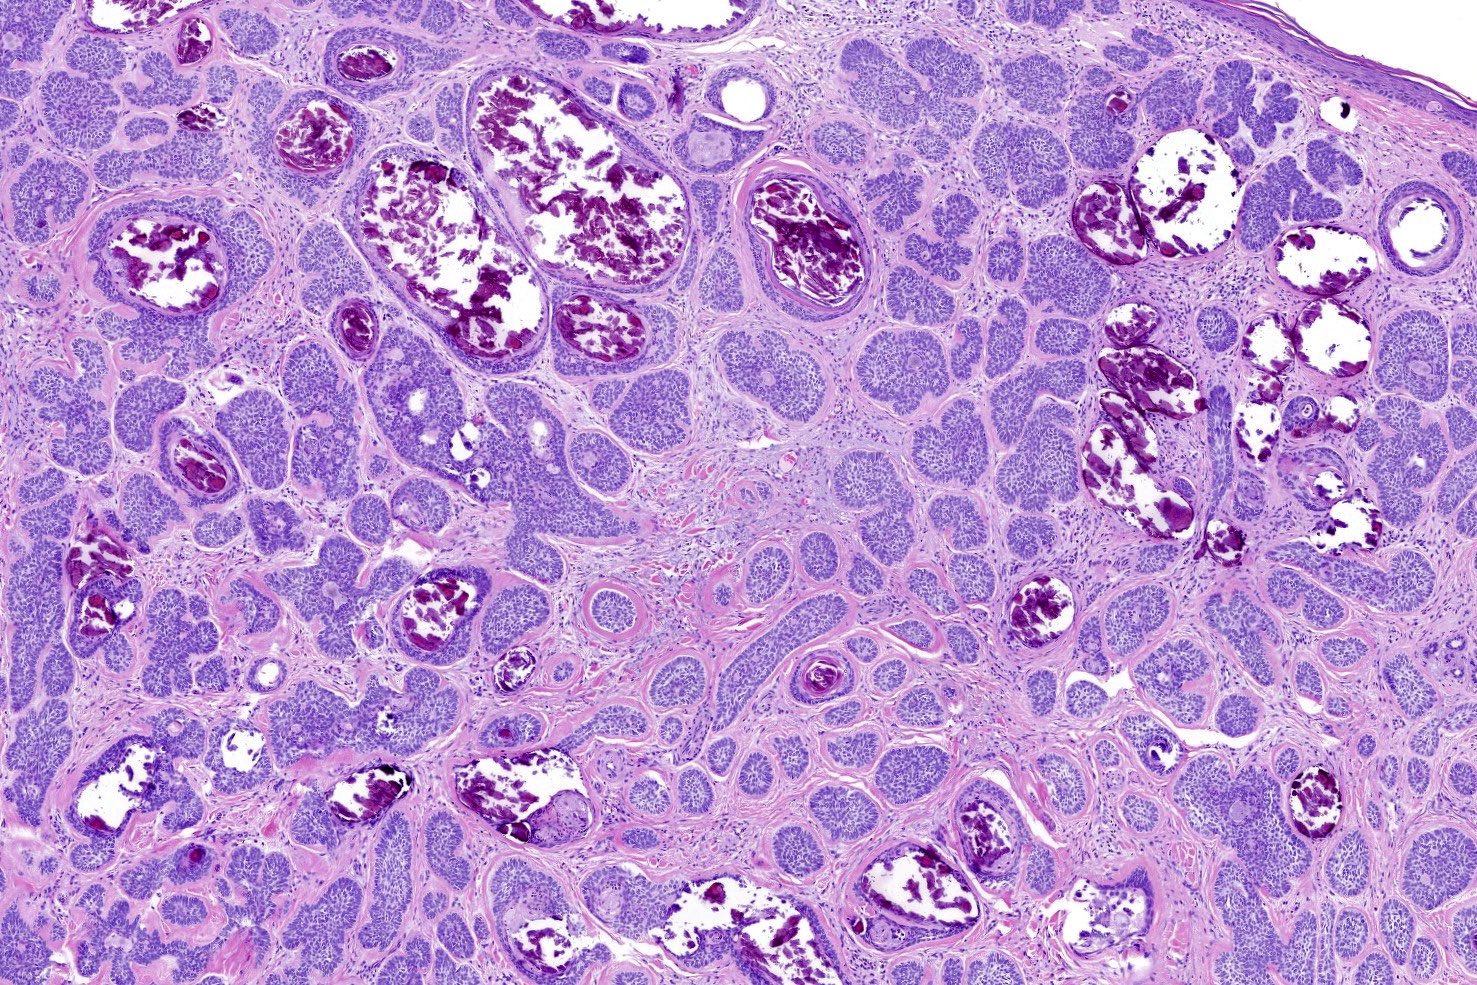

A 67-year-old male presents to your hand clinic for a trigger finger that is preventing him from holding his golf club. During your examination, you notice a 1 cm x 1 cm erythematous plaque on the dorsum of his hand. Upon further questioning, you learn the patient retired ten years ago after a successful kidney transplant and volunteers at his local golf course. You are concerned about the lesion and send him for a biopsy which is shown in Figure A. What is the most likely diagnosis given his history and the provided histologic slide?

The patient’s history of UV exposure and solid organ transplant put him at high risk of developing squamous cell carcinoma (SCC, Answer 1). The histology demonstrates keratin nodules and confirms the diagnosis of SCC.

Figure A is a histologic slide of SCC showing keratin nodules with large vesicular nuclei and eosinophilic cytoplasm.

Illustration A shows a histological slide of basal cell carcinoma (BCC). Typical to BCC are islands of basal cells arranged randomly in the centers of the islands, with palisading at the periphery. Illustration B is the histology of melanoma demonstrating nests of melanocytes with numerous mitotic figures. Illustration C shows the histology of seborrheic keratosis with numerous proliferations of epidermal keratinocytes. Illustration D shows lentigo with an increase in basal melanin with a mildly increased number of melanocytes in the basal layer of the epidermis.